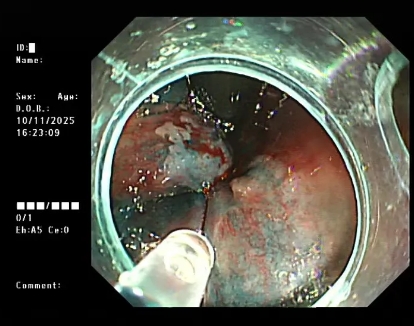

图片

△内镜下硬化治疗